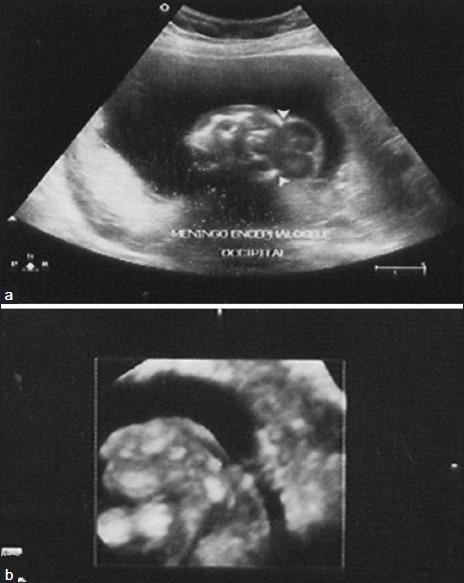

Meckel Gruber syndrome (MKS) is a lethal, autosomal, recessive, multisystemic disorder, associated with mutations affecting ciliogenesis. Since the time it was first reported; only 200 cases have been reported. From January 2004 to December 2010, we evaluated 268 fetal autopsies in our institute, in the Department of Pathology; two of these fetuses were diagnosed as MKS. MKS is characterized by occipital meningoencephalocele, cystic kidneys, postaxial polydactyly, and fibrosis in the liver. MKS cases show genetic heterogeneity. MKS results in 100% fetal or neonatal mortality. As MKS has a high risk (25%) of recurrence; parents should be counseled for future pregnancies.

梅克尔-格鲁伯综合征(MKS)是一种致死性常染色体隐性多系统疾病,与影响纤毛发生的突变有关。自首次报道以来,仅报告了200例病例。2004年1月至2010年12月,我们在我院病理科对268例胎儿尸体解剖进行了评估,其中有2例胎儿被诊断为MKS。MKS的特征为枕部脑膨出、多囊肾、轴后多指畸形和肝脏纤维化。MKS病例表现出遗传异质性。MKS导致100%的胎儿或新生儿死亡。由于MKS有较高的复发风险(25%),因此应对父母进行关于未来妊娠的咨询。